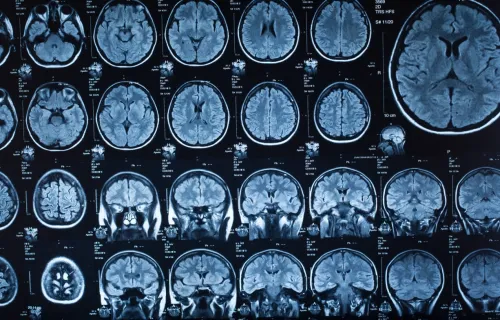

- Improve diagnostic accuracy and clinical decision-making